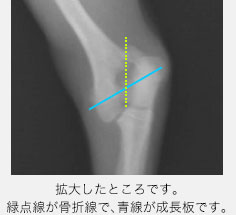

青いラインが成長板です。数字が大きいほど後の障害が出やすいと言われています。 Type5は、強い圧力が加わることで成長板が機能しなくなるタイプです。

今回ご紹介する症例は5ヶ月齢のトイプードルで、散歩中に道路の側溝に落ちてから左前肢を挙げるとのことで来院されました。触診では左前肢の肘の部分を痛がり、レントゲン検査を行ったところ、左上腕骨の成長板骨折と分かりました。先ほどのSalter-Harris分類のType4で、成長板が斜めに折れていました。